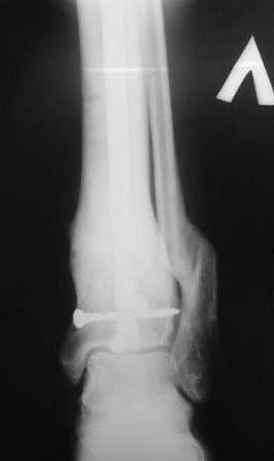

5, 6 - через 2,5 мес после травмы выполнен закрытый остеосинтез блокируемым штифтом.

7, 8, 9, 10, 11 - через 8 мес после травмы перелом сросся.

Пациент ходит без дополнительной опоры, не хромает (видеоролик выложил сюда

-->> дистальный фрагмент слишком короткий, меньше 2 см, нет места для интрамедуллярного штифта, в отличии от пациента Др. Иванова (прекрастный результат!).

Согласен с тобой, короткий дистальный фрагмент, нет места ни для штифта, ни Т-образной пластины, да и шурупы мешают.

Срок маленький, с преждевременным удалением шурупов можно потерять репозицию эпифиза.